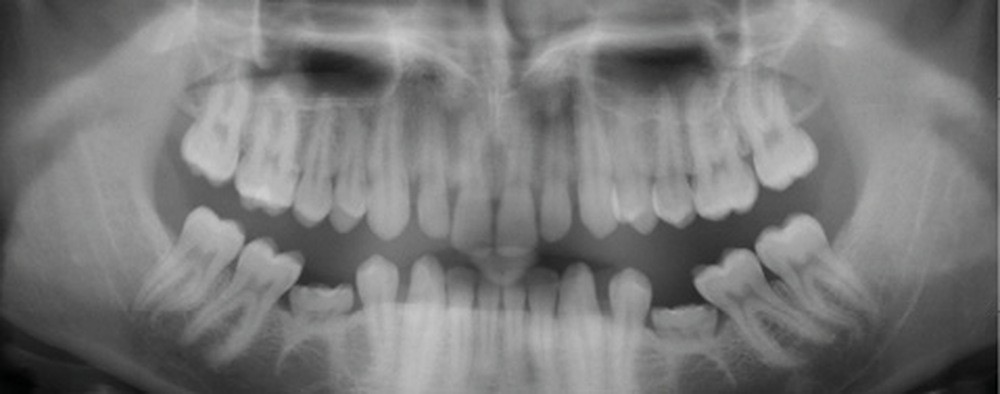

Quand un traitement orthodontique est indiqué dans le cadre de la persistance d’une molaire temporaire, l’orthodontiste doit toujours choisir entre deux solutions : maintenir ou fermer l’espace d’agénésie. Malheureusement, il est parfois confronté à une indication de maintien de l’espace d’agénésie, alors que la dent temporaire ne peut pas être maintenue jusqu’à la fin de la croissance (pour cause de caries, de réinclusion sévère, de perte, etc.) (fig. 1). La pose d’un mainteneur d’espace en fin de traitement est nécessaire, mais rien ne maintient l’os jusqu’à la fin de la croissance et la pose implantaire ! Les patients se retrouvent alors obligés de recourir à des préparations osseuses préimplantaires parfois lourdes. Le but de cet article est de proposer des solutions de maintien du volume osseux après avulsion de la deuxième molaire temporaire.